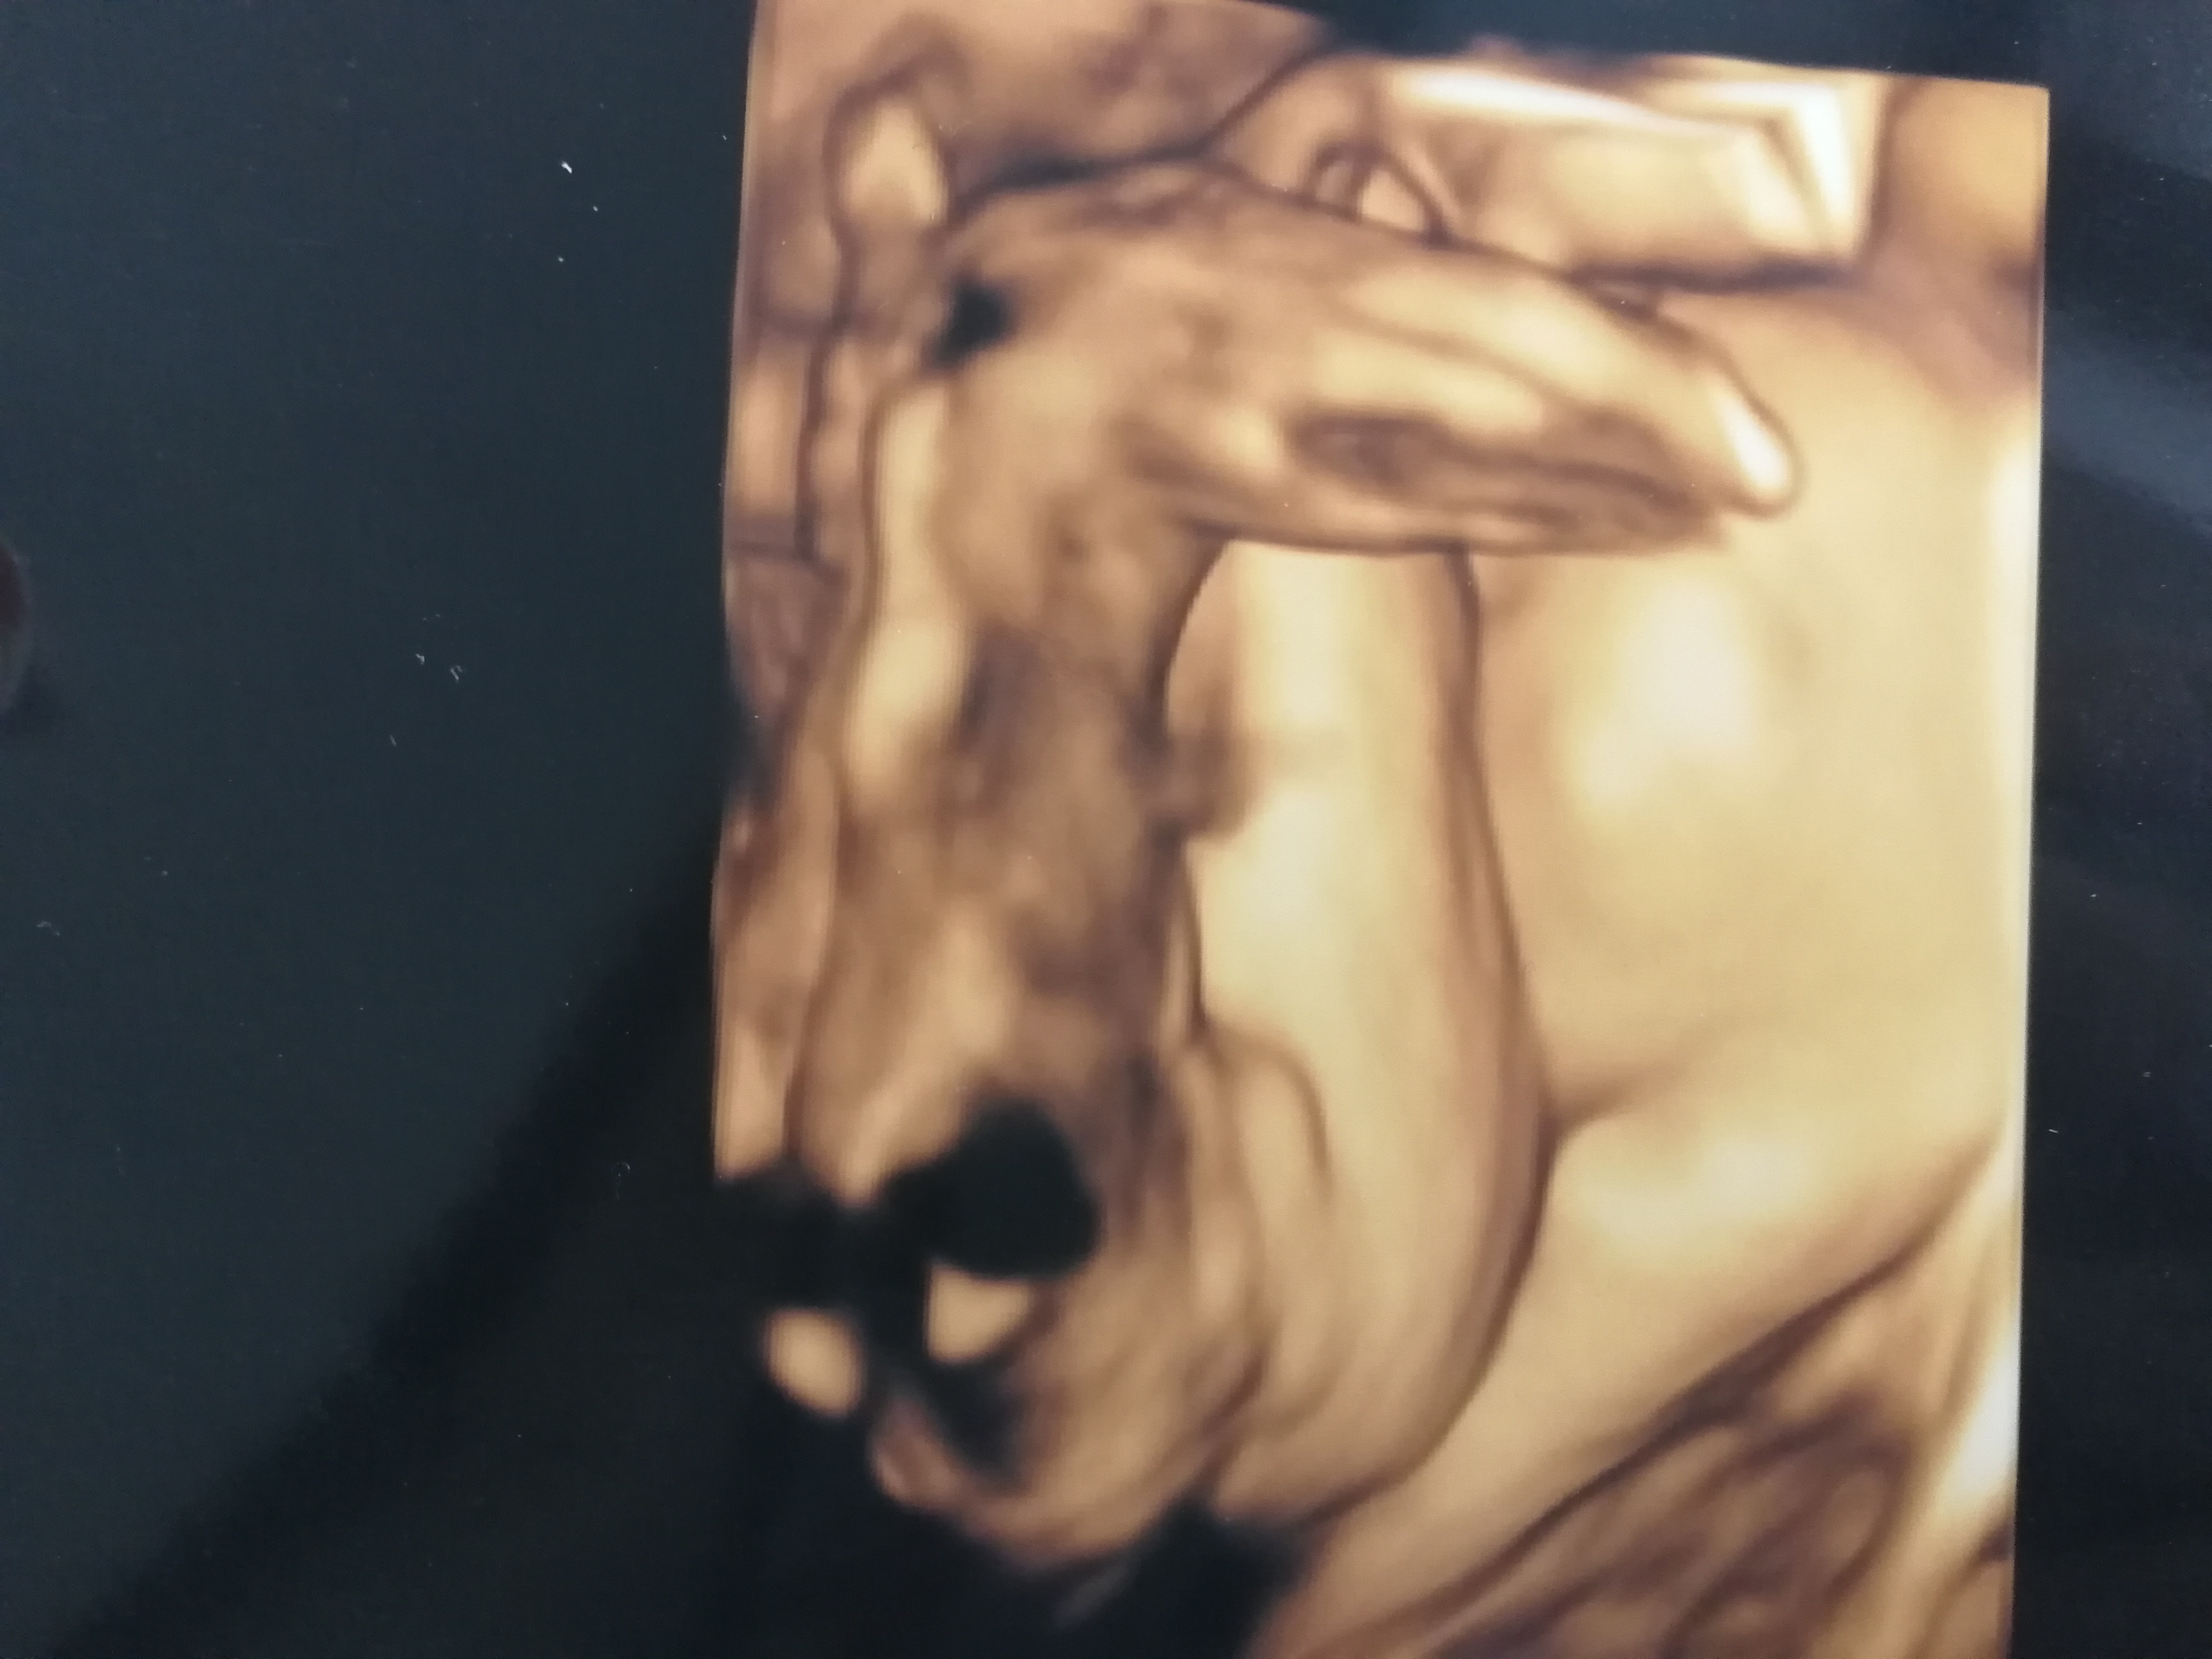

Ahoj. Jsem v 30tt a podle doktora a utz čekáme holčičku.. Ale všichni kolem mě mi furt říkají že to určitě bude kluk, dokoce i ja sama od začátku cítím, že to bude kluk 😁 uz mi asi hormony lezou hodně na mozek. Tak by mě zajimal i váš názor podle fotek.. Je to fakt holčička? Nemá ty pysky nějaké natekle, nebo měl nekdo podobný případ a nakonec se narodil kluk? Fotky jsou z 24tt. Od te doby se mimčo na utz neukazalo jestli tam dorost pindík nebo ne.

A není to jedno, co to bude? Já tam vidím holku, na té žluté fotce se to prostě nedá přehlédnout ... Hlavně, aby bylo mimčo zdravé. To je mnohem důležitější než znalost pohlaví před porodem.

• U kluka by jsi ty kulky fakt neprehledla. Jsou v tom 24tt už dost výrazné. Věřila bych doktorům, než v mnoha případech zboznemu přání dalších členů rodiny, aby to byl kluk.

• Na UZ jsou celkem jasne videt pysky. Mam 2 kluky a ver mi, ze koule vypadaji uplne jinak. A hlavne se tes na miminko a prestan se stresovat pohlavim a tim, co do tebe hrne okoli 😉